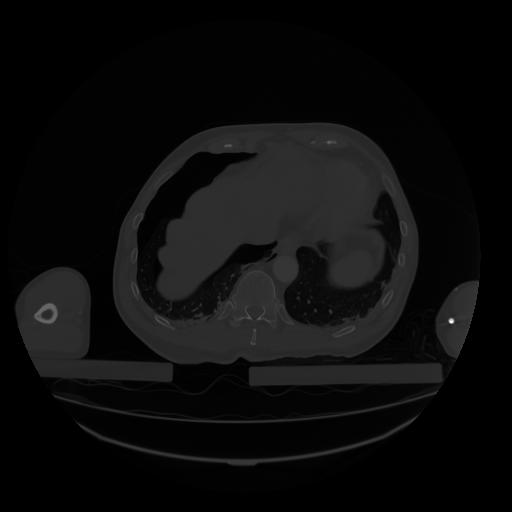

28 CUERPO,CE,Vol,2.0,CUERPO,,